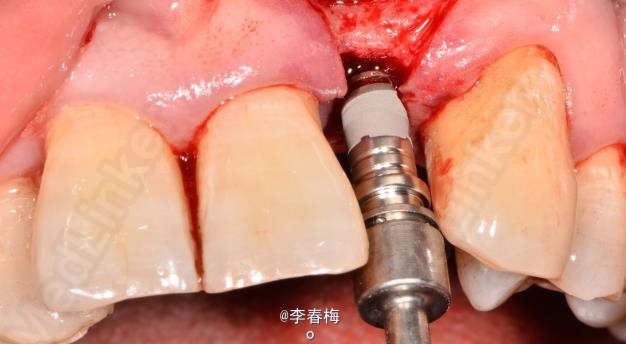

上颌前牙种植修复

患者,男,左上颌侧切牙缺失来诊。平素体质一般,无药物、食物过敏史,无高血压、心脏病等系统性疾病。